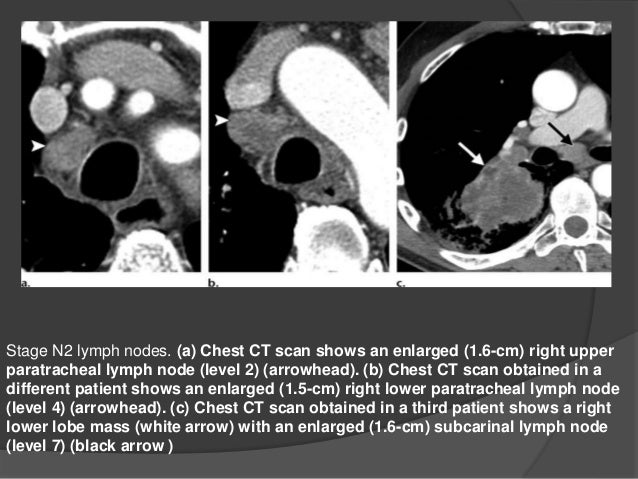

Non Small Cell Lung Cancer Staging Stages Of Lung Cancer